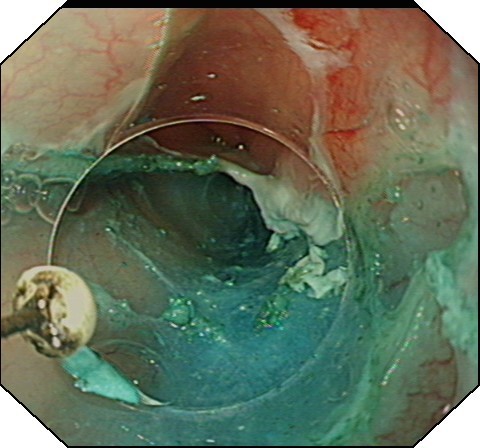

大家都知道,人体胃壁共有四层组织组成:由内到外分别为粘膜层、粘膜下层、肌层、浆膜层。胡妈妈的肿瘤就长在肌层,这是一种良性的胃肿瘤。通常,传统治疗方法一般建议外科手术治疗,开腹或开胸,有时还需要切除食管或者胃的一部分,创伤大,费用高,恢复期长。消化科吕宾教授对患者的检查资料进行仔细的研究分析,在获得患者的知情同意后,决定用国际内镜治疗的最新技术——经内镜粘膜下隧道肿瘤剥离术(STER)切除肿物。STER是通过在距肿瘤近口侧约3-5cm切开粘膜,建立粘膜下隧道(图1),逐步分离组织,显露肿瘤,再沿肿瘤包膜在内镜直视下剥离,完整剥离后取出肿瘤(图2),用金属夹关闭隧道口(图3)。

图1 建立隧道 图2 分离肿瘤